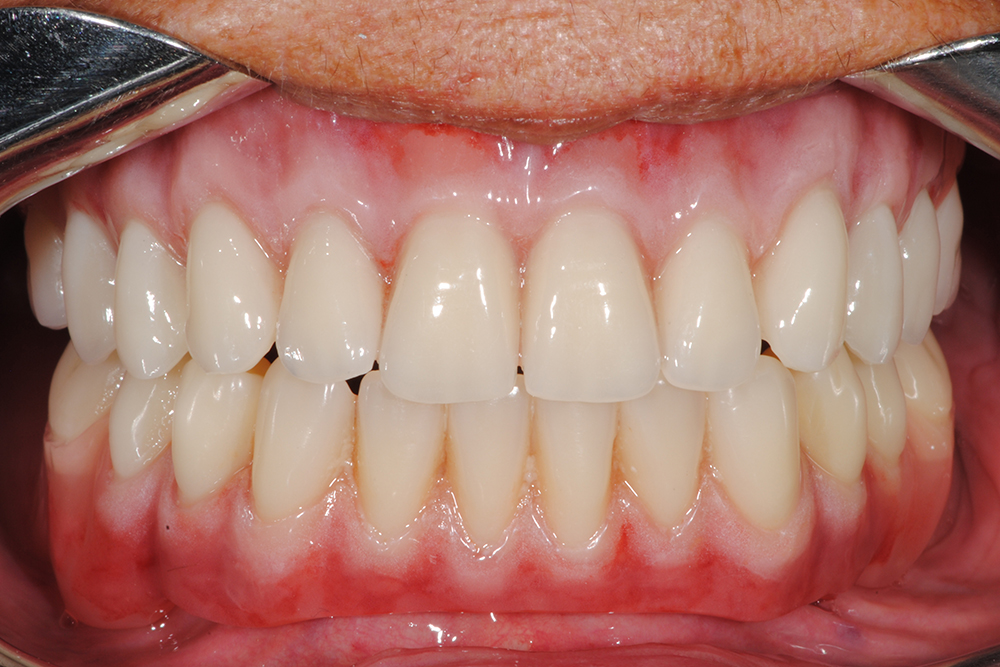

Ripristino dell’arcata superiore ed inferiore su overdenture su barra